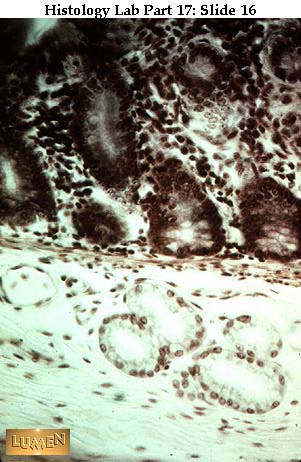

Slide 16

Detail of dark intestinal glands (crypts of Lieberkuhn) above and pale Brunner's alveolar units below the thin pink line of muscularis mucosae. Brunner's glands empty their mucous contents into the crypts. Their secretion is somewhat alkaline to neutralize the highly acid contents entering the duodenum from the stomach.